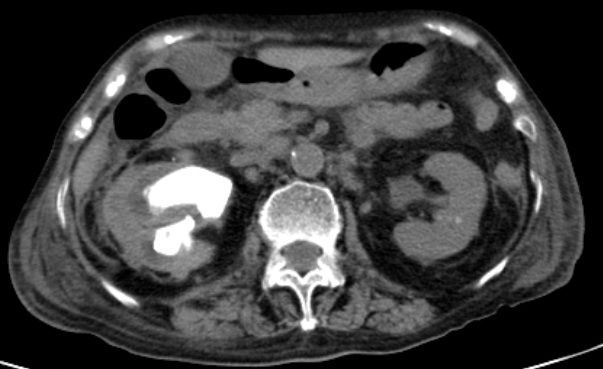

住院后完善检查后发现,患者3年前因右肾结石并积脓感染在外院行右肾穿刺造瘘后1月拔出造瘘管,之后从造瘘管持续流出脓液至今,单单是更换纱布的花费已有2万余元。

因患者存在严重的泌尿系感染,长期感染致使患者出现严重营养不良及毒素缓慢吸收的中毒表现,遂全科讨论后首先尝试行右侧输尿管支架植入术以求内引流控制感染,但效果不佳;果断再次行右侧肾穿刺造瘘引流局部感染物质控制感染!

感染初步得到控制后,

明确患者右侧肾铸形结石

并右侧无功能肾,

黄色肉芽肿性肾盂肾炎( xanthogranulomatous pyelonephritis,XGP) 是一种少见的由细菌感染引起的肾实质及肾周组织慢性非特异性炎性病变,约占所有肾感染的0. 6% ~ 1. 4%,由于发病率不高,缺乏特异的影像学表现,常常被误诊为恶性病变。

当患者出现发热、腰疼、血尿、脓尿、尿路刺激症状以及合并慢性泌尿系梗阻症状时,结合以下声像图改变,包括肾形态饱满、肾盂扩张积水,扩张集合系统内具有低回声,尤其发现病人有泌尿系梗阻原因及肾结石时,可以考虑到XGP 的可能性。CT 和超声造影可能有助于进一步明确疾病的诊断,最终确诊仍需依靠超声引导下穿刺或手术的病理报告。